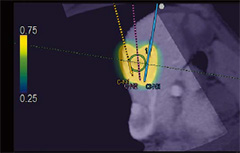

・E-field Simulator

RFA治療時の電極の配置から決定される電気的物理量(電場)をCTなどの画像上に表示します。複数本穿刺の際にもあらゆる電極配置に合わせて電場をシミュレーション可能なので,穿刺ライン検討の自由度が大幅に高まります。

これまでの手技を大幅に改善することが期待されます。